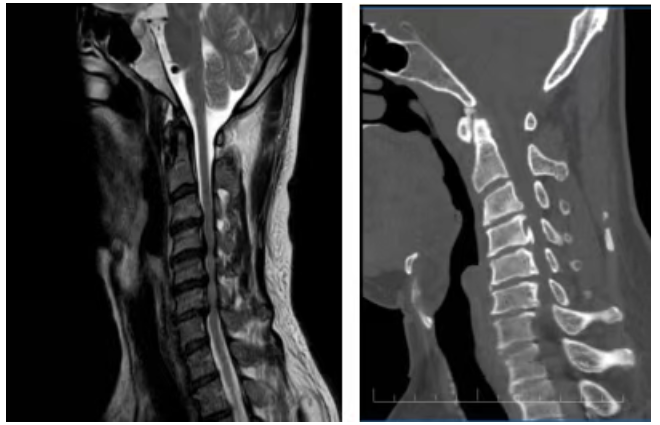

患者赵先生多年来饱受颈椎病的困扰,随着病情不断加重,肢体麻木无力的症状日益显著,日常行动不便,严重影响生活质量。在辗转多地就医后,赵先生来到长沙市第一医院脊柱外科就诊。经全面检查,患者被确诊为严重的颈椎后纵韧带骨化症,其颈部脊髓在核磁影像中呈现出惊人一幕——颈部脊髓被巨大骨化物压迫形似一根“细线”,任何细微的外力都可能瞬间引发四肢的瘫痪。

“颈椎里的后纵韧带原本是一层软性的韧带组织,起到防止突出的椎间盘等组织向后挤压脊髓的作用,但赵先生的韧带已经变成了坚硬的骨头,而且还在不停增厚,从C3到C7五个节段骨化,像一把枷锁死死压住了脊髓。”脊柱外科副主任蒋成明介绍,传统前路手术需直接切除骨化物,脊髓损伤风险高,同时脑脊液漏的风险也很高;后路手术虽然安全些,却无法彻底解除压迫。

前沿技术的前后对比图